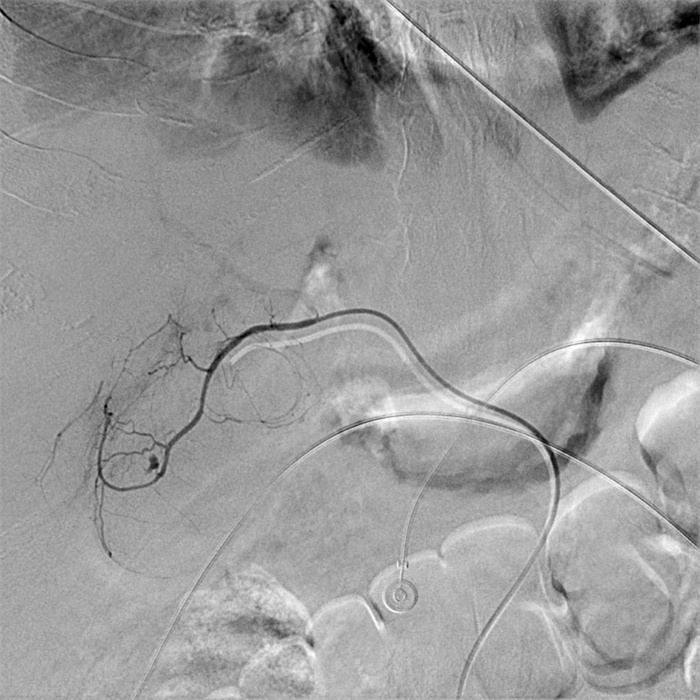

入院第57天,患者再次出现暗红色血便,伴阵发性右上腹痛,无发热、呕血,症状与之前相同。鉴于患者有活动性出血,再次复查胃镜:慢性浅表性胃炎伴糜烂。复查肝功能:γ-GT 844 U/L,TBil 43.6 μmol/L,NCBil 16.6 μmol/L,CBil 27 μmol/L,肝功指标再次回升,γ-GT、CBil明显升高,提示可能出现胆道梗阻。肝胆脾胰腺彩超复查:胆囊肿大、胆囊陈旧性稠厚淤胆(较前无明显变化),胰腺稍大并不均质改变。复查上腹CT:AP复查情况与之前相同,可能有胆囊出血(见图 2)。联合介入放射科行血管造影检查,常规局部麻醉下采用Seldinger技术由右侧股动脉入路,造影发现胆囊动脉分支出血(图 3),超选择胆囊动脉分支用明胶海绵颗粒行栓塞止血(图 4)。同时,行经皮经肝胆囊穿刺置管引流(图 5),病情稳定后带管出院,3月后予以拔除,择期行胆囊切除。

| 胆囊动脉增粗,其分支局部造影剂外溢,未见明显动脉瘤征象 图 3 胆囊动脉造影 |